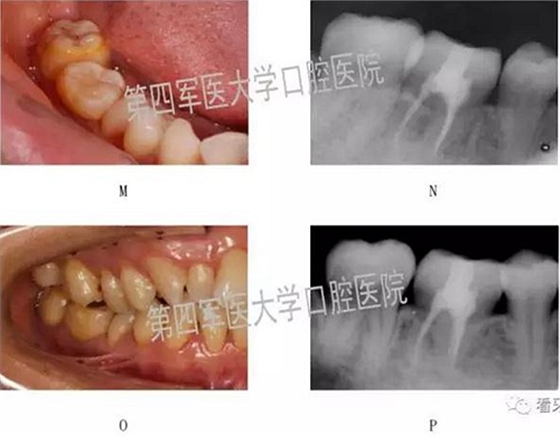

二,牙槽內(nèi)移植

1,阻生牙牽出再值